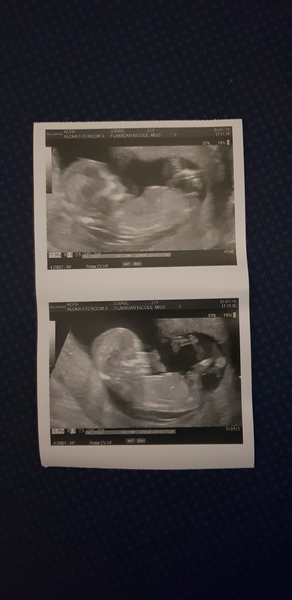

Hello - we're having our sexing scan next Friday but would love to see if any of you have any guesses on our baby!

We've had a lot of mixed opinions!

Skull theory